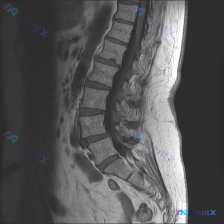

整理到一张腰椎MRI T2加权序列冠状位的影像资料,先不看后续的其他序列和临床信息,只看这张图的话,有几个点比较值得拿出来讨论: 1. 脊柱力线确实有明显异常,侧弯方向和顶端位置也比较清楚 2. 椎间盘的信号和椎间隙高度有非对称性改变 3. 扫描野里除了腰椎,还能看到双侧肾脏,肾盂肾盏区似乎有信号变...